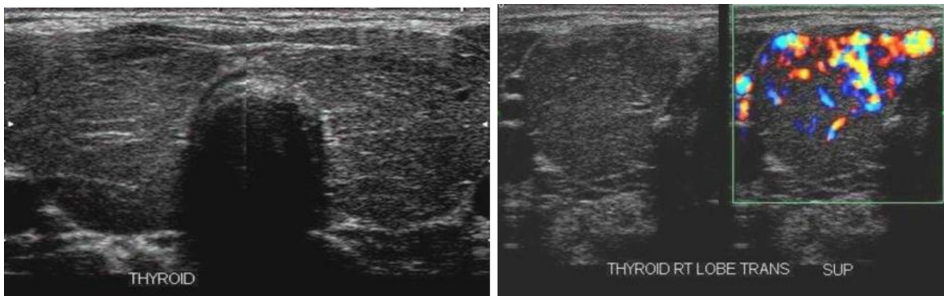

研究主要采用四种关键技术:1)甲状腺功能检测(TSH<0.01 mIU/L,T4 58 pmol/L)确认甲亢状态;2)电生理检查显示神经肌肉传导显著衰减(19-62%);3)抗AChR抗体检测(16.9 nmol/L)确诊MG;4)超声与核素显像显示甲状腺"火海征"和均匀高摄取。

电生理检查在眼轮匝肌和拇短展肌记录到特征性递减反应,符合MG诊断标准。甲状腺核素扫描显示均匀高摄取,同时排除了胸腺瘤可能。免疫学检测除AChR抗体外,还发现抗U1-RNP抗体(9 IU),提示更广泛的自身免疫倾向。